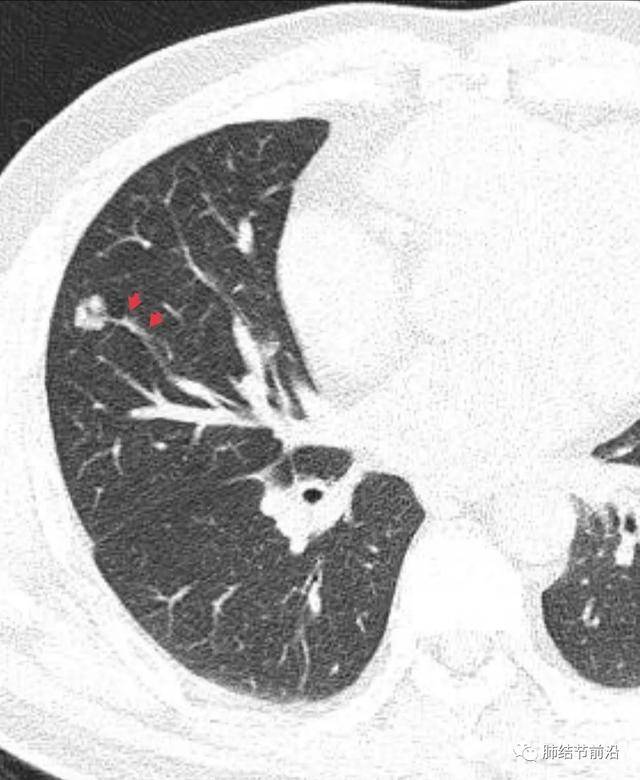

什么是肺結(jié)節(jié)呢?肺結(jié)節(jié)是指肺部出現(xiàn)的一種直徑小于或等于3厘米的圓形或近似圓形的病灶,大多數(shù)肺結(jié)節(jié)是良性的,只有一小部分可能是惡性的。

肺結(jié)節(jié)的診斷

診斷肺結(jié)節(jié)主要依賴(lài)于醫(yī)學(xué)影像技術(shù),如X光、CT等,醫(yī)生會(huì)根據(jù)患者的病史、體征和影像學(xué)表現(xiàn)進(jìn)行綜合判斷,對(duì)于疑似惡性的結(jié)節(jié),可能需要進(jìn)行進(jìn)一步的檢查,如活檢等。